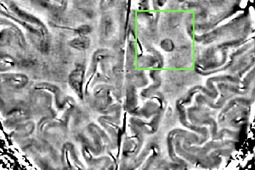

Celem badania przeprowadzonego przez Nielsen i wsp. było wykorzystanie rezonansu magnetycznego w polu o indukcji magnetycznej 7 Tesli (T) w celu określenia charakteru zmian korowych u pacjentów ze stwardnieniem rozsianym. Skan wykonano u 27 pacjentów z nawracająco-remitującym lub pierwotnie postępującym stwardnieniem rozsianym w różnym stadium zaawansowania. Dane zbierano techniką FLASH (fast low-angle shot), uzyskując T2-ważone obrazy kory mózgu. W okresie tygodnia po badaniu metodą rezonansu magnetycznego chorzy byli poddawani ocenie neuropsychologicznej i fizykalnej. Stwierdzono zależność między występowaniem zmian korowych typu III i IV a niepełnosprawnością, którą charakteryzowało ρ Spearmana wynoszące 0.67 (p < 0.0001). Zaobserwowane zmiany korowe typu pierwszego oraz ogniska demielinizacji w istocie białej były związane z pogorszeniem w zakresie 6 z 11 parametrów oceny neuropsychologicznej. Zmiany korowe typu II, a także objętość zmian w istocie szarej, nie były związane z ocenami uzyskiwanymi w testach neuropsychologicznych. Nielsen i wsp. wywnioskowali z przeprowadzonych obserwacji, że zmiany korowe typu I, III i IV obserwowane w obrazach uzyskanych techniką rezonansu magnetycznego w polu o indukcji 7 T mogą stanowić markery stanu klinicznego u pacjentów ze stwardnieniem rozsianym.